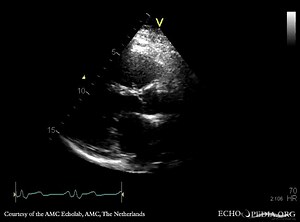

Atrial Septal Defect (ASD) on Echocardiography | Congenital He

…

Sinus Venosus Atrial Septal Defect (SV ASD)

ASD Vs PFO